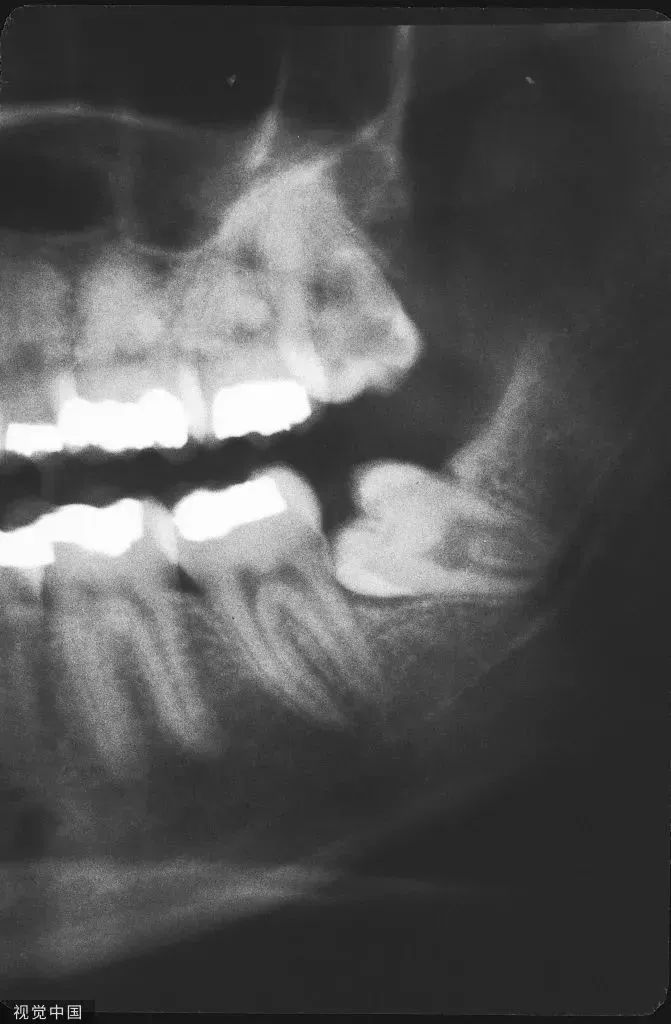

正常的恒牙总共有28颗,如果你发现牙齿多于28颗,那就是长出了智齿,这时候你需要密切关注它的萌出状态,最好是去专门的医院拍片确认其是否正常,听从医师的建议选择拔或不拔。如果牙齿出现疼痛、炎症等,也应及时就诊,早期发现不正常的智齿,早点拔除,可以防止后续出现更多麻烦。

4.完善术前检查,如口腔全景片、CT来评估手术风险;